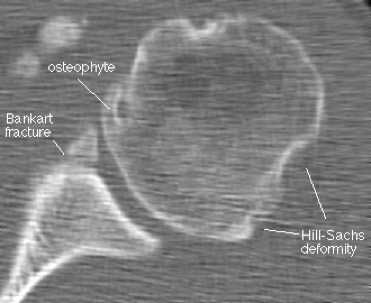

Наиболее типичным (около 85% передних смещений травматической этиологии) является повреждение Банкарта - отрыв фиброзного или фибрознохрящевого фрагмента от края суставной впадины в месте прикрепления связки к суставной впадине с повреждением суставной губы. Кроме того, травма может приводить и к костным повреждениям - перелому гленоидного кольца спереди, костному повреждению Банкарта (то есть повреждению Банкарта в сочетании с переломом) и перелому большой бугристости.

МРТ плечевого сустава. Корональные Т1-взвешенные МРТ. Переломы Хилла-Сакса и Банкарта.

На КТ хорошо видны костные дефекты и дефекты гиалинового хряща суставной впадины. Гиалиновый хрящ, покрывающий головку плечевой кости виден гораздо хуже.

КТ плечевого сустава, Переломы Банкарта и Хилла-Сакса.